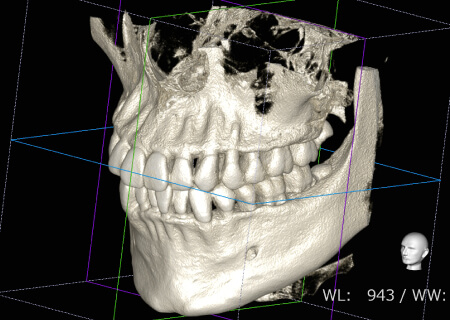

術前のカウンセリングで、抜歯の必要性を診査診断し、抜歯の必要がある場合、顎の神経に歯の根元が近くないかを確認し、安全に処置を進めていきます。歯の角度や根っこの形状をあらかじめ調べ、迅速かつ安全に抜歯します。当院では手術室をはじめ大学病院並みの設備を完備しており、抜歯における生体モニターやCT設備、検査機器を揃えています。滅菌された器具で清潔な環境を徹底しているので、安心して外科手術に臨んでいただくことができます。

埋もれている親知らずの歯の抜歯、口腔内の手術などを行う場合には、まずコンピューターでシミュレーションを行います。さらにCT画像︎を処理することで様々な角度から画像を分析し、より安全に治療を行うことが可能です。